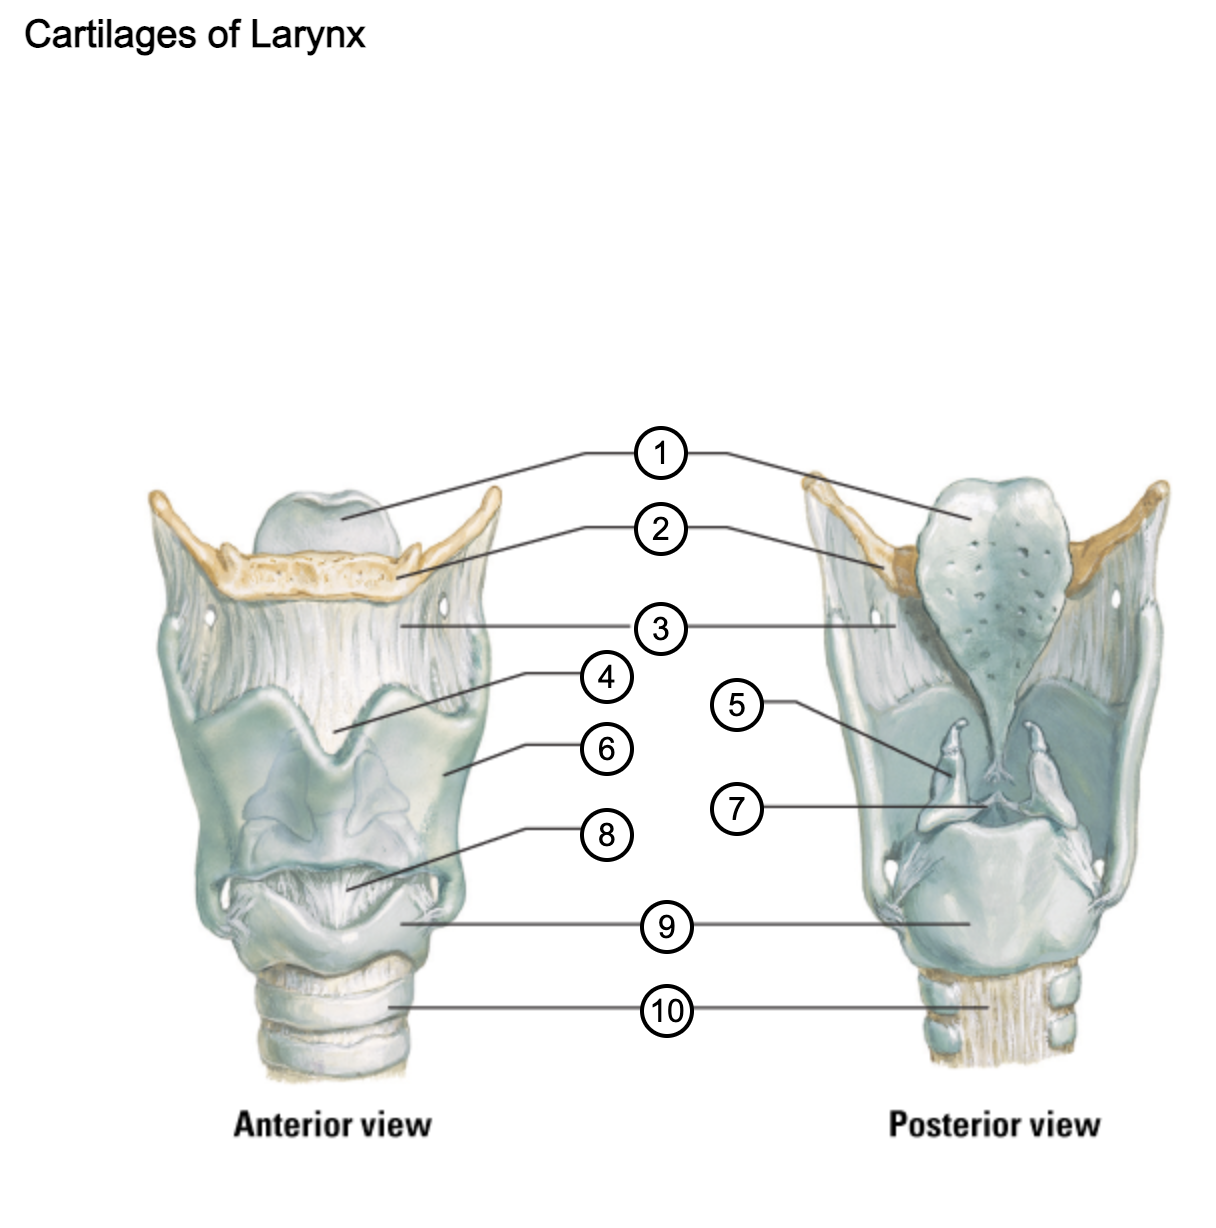

1

epiglottis

2

hyoid bone

3

thyrohyoid membrane

4

superior thyroid notch

5

arytenoid cartilage

6

lamina of thyroid cartilage

7

vocal ligament

8

median cricothyroid ligament

9

cricoid cartilage

10

trachea